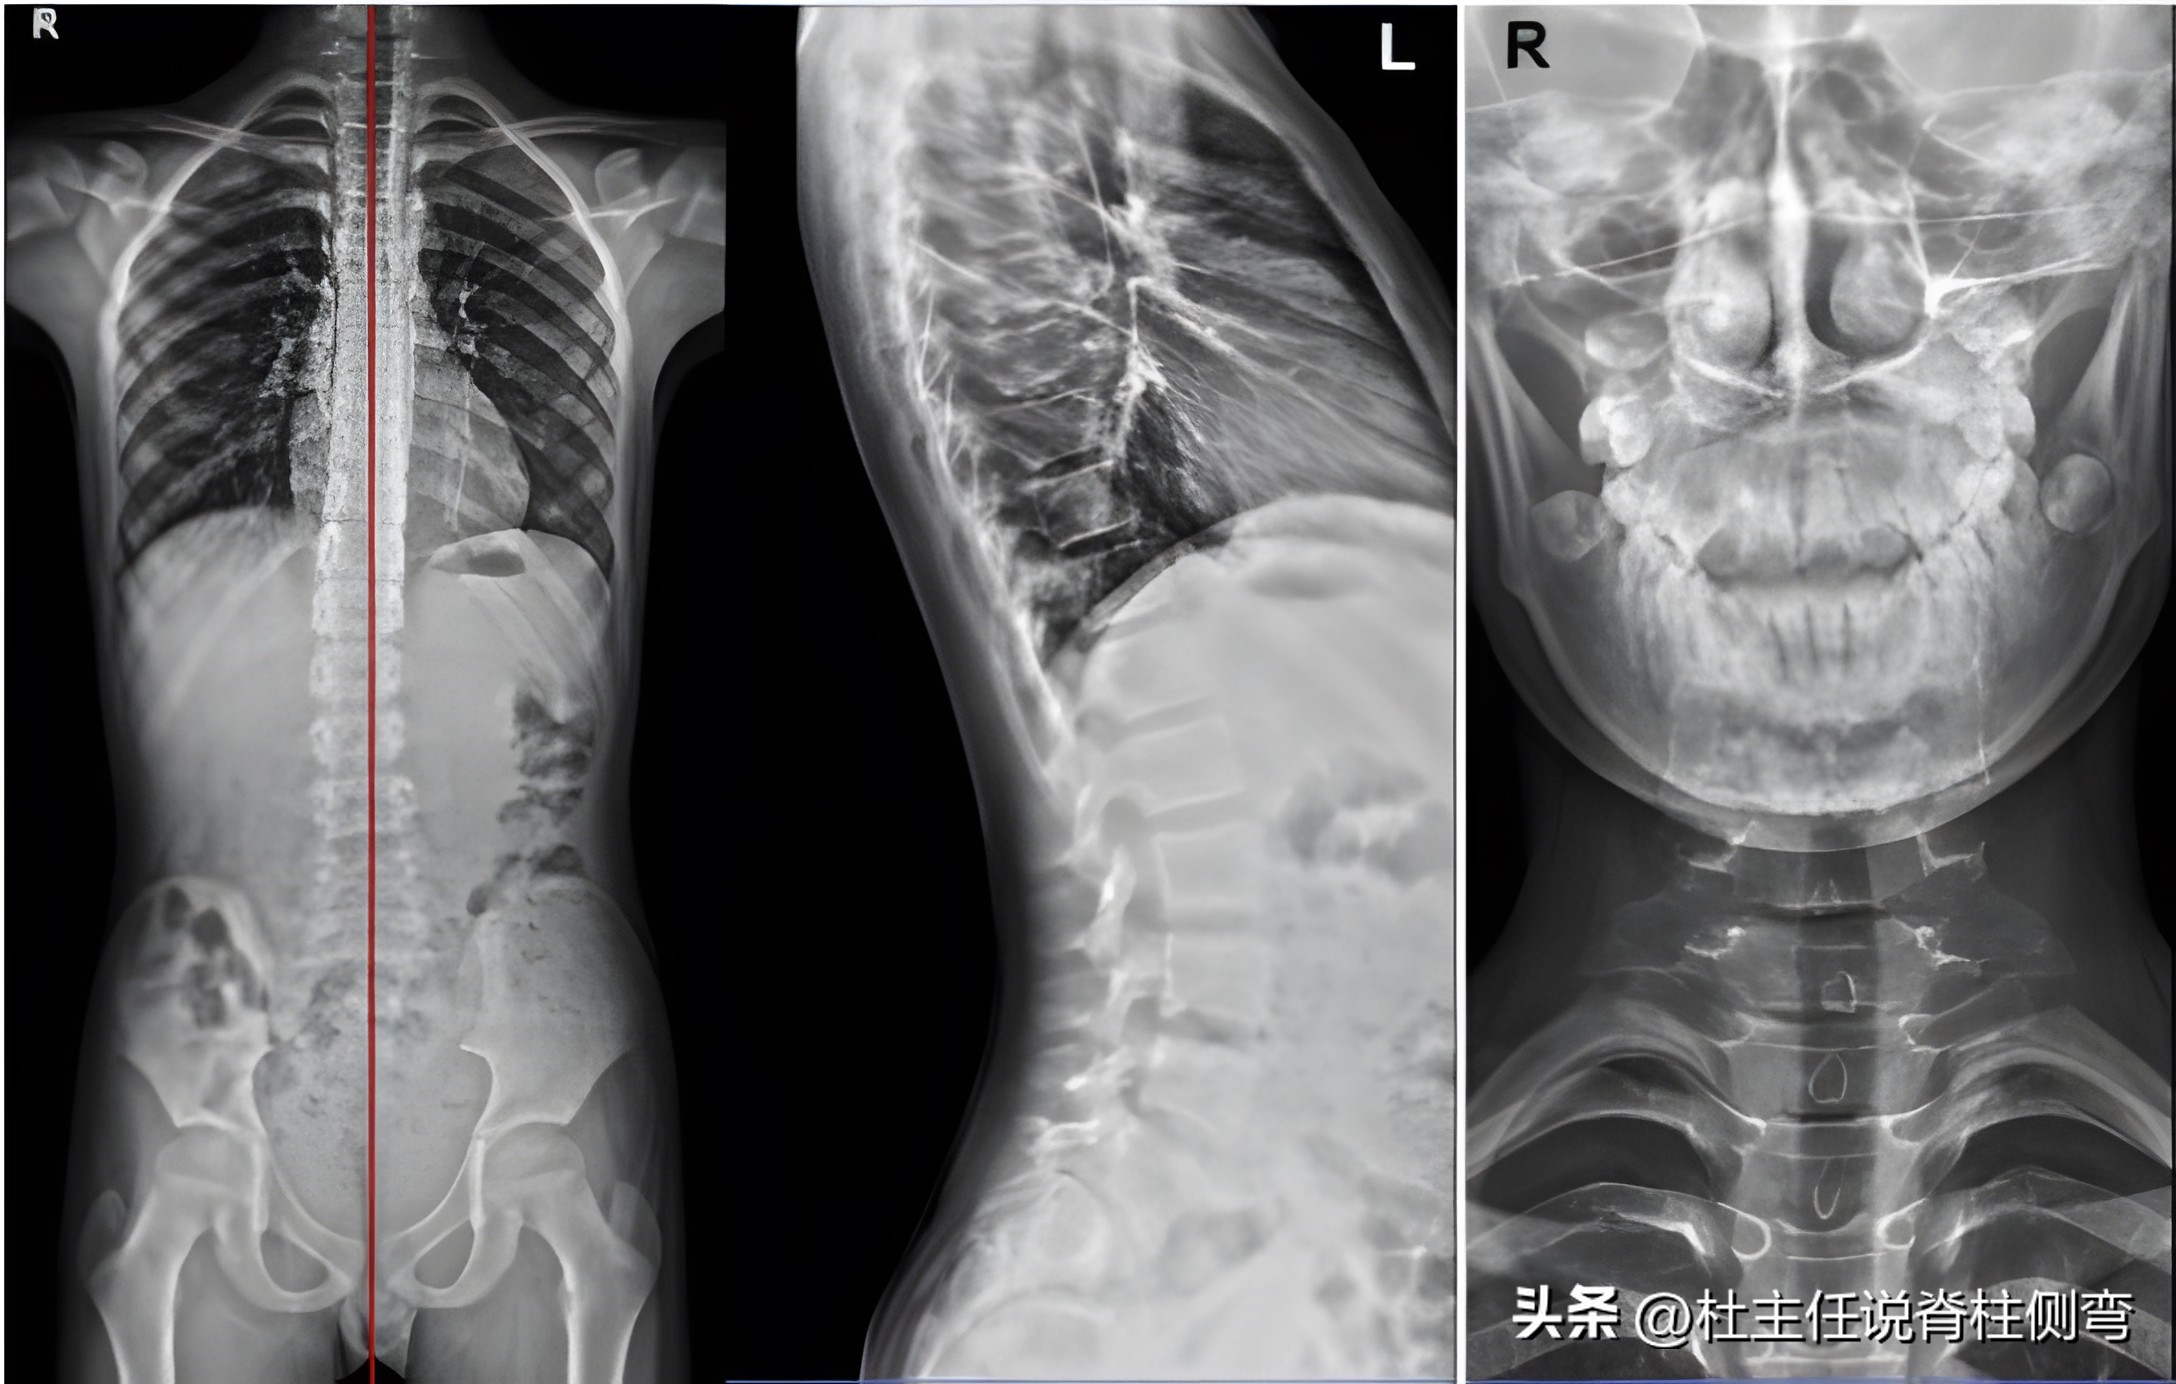

2、 X光片检查: 以L1为中心向右侧凸,Cobb角约12°,Risser征:0级,脊柱整体向中线右侧偏移。风险系数:0.94;两侧闭孔右大左小。胸椎、腰椎生理曲度存在。

而且年龄小,身体柔韧性和关节相对柔软,所以由X光片可见,以L1为中心向右侧凸,Cobb角约12°,度数不算大,风险系数:0.94,尚未达到佩戴支具的标准(佩戴支具标准:风险系数≥1.6)。